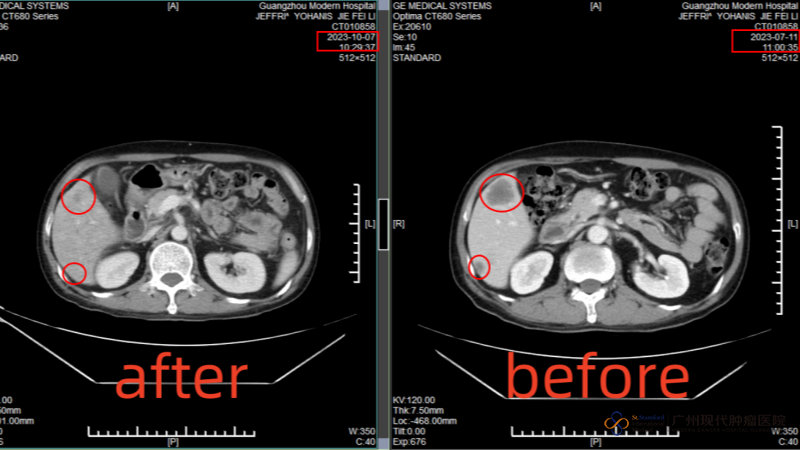

After I arrived at the hospital, the MDT medical team of the hospital consulted me and formulated a comprehensive treatment of "intervention + cryotherapy". Before the treatment, the tumor in the anus was about 29mmx38mm, but after an intervention, the tumor was reduced to 13mmx17mm, and the multiple metastatic foci in the liver were mostly invisible on CT after cryotherapy. Both my wife and I are very happy with this result.

[Comparison of liver tumor size after the first cryotherapy]